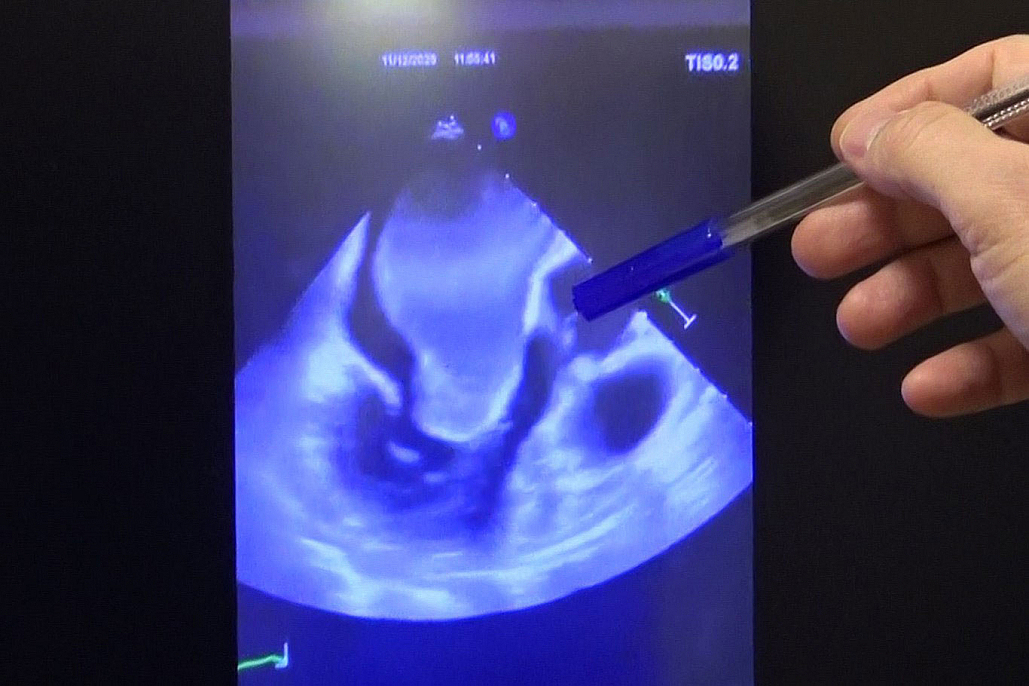

Türkiye'de bir ilk Malatya'da gerçekleştirildi. İnönü Üniversitesi Turgut Özal Tıp Merkezi'nde, kalbin içini tamamen kaplayan devasa bir kitle Türkiye'de ilk kez gerçekleştirilen başarılı bir operasyonla çıkarıldı.